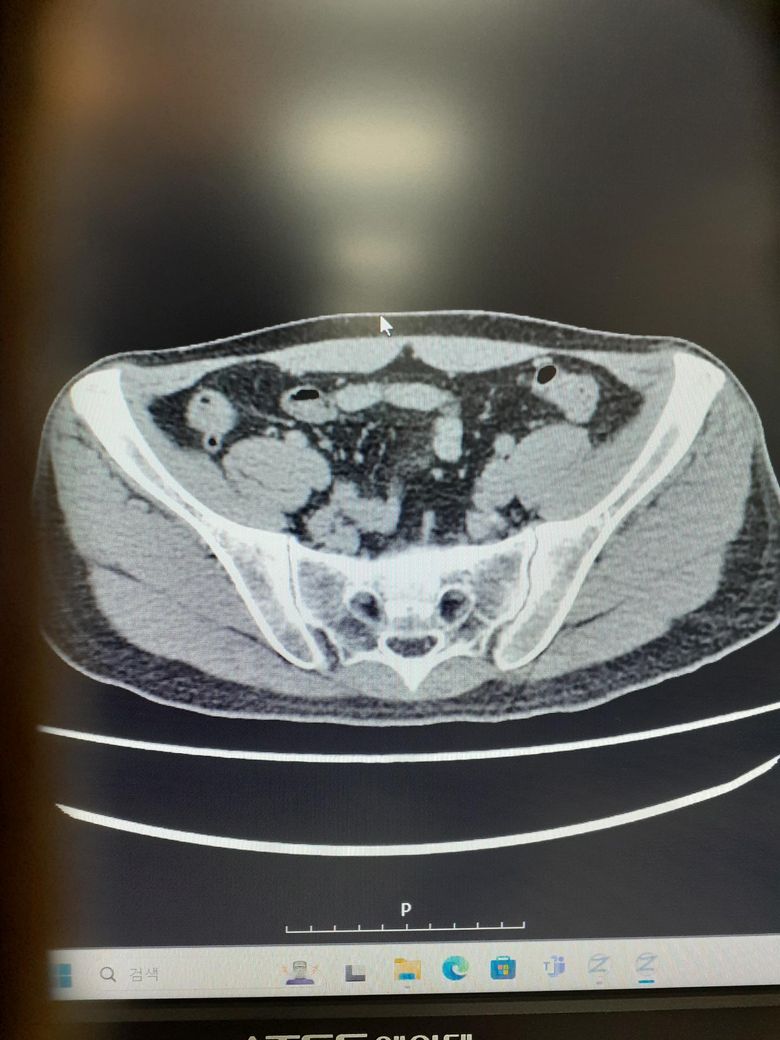

ct사진좀봐주세요사례합니다 조영제십니다

이상 없다고집으로보냅니다 전립선난종과만성담낭염같은데이상 없다내요왜그러죠

소변통 성관계통증도잇는데최근에복부통증이심해졋어요